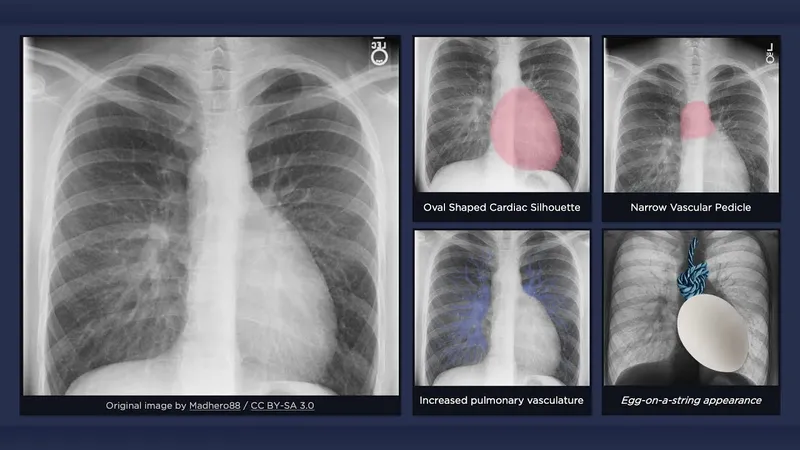

| TGA | "Egg on a string" (narrow mediastinum), ↑PBF. 📌

| Aorta from RV (anterior), PA from LV (posterior). |

- Transposition of Great Arteries (TGA): "egg-on-string" sign on CXR.

- Cardiac Silhouette: e.g., "boot-shaped" (TOF), "egg-on-string" (TGA).